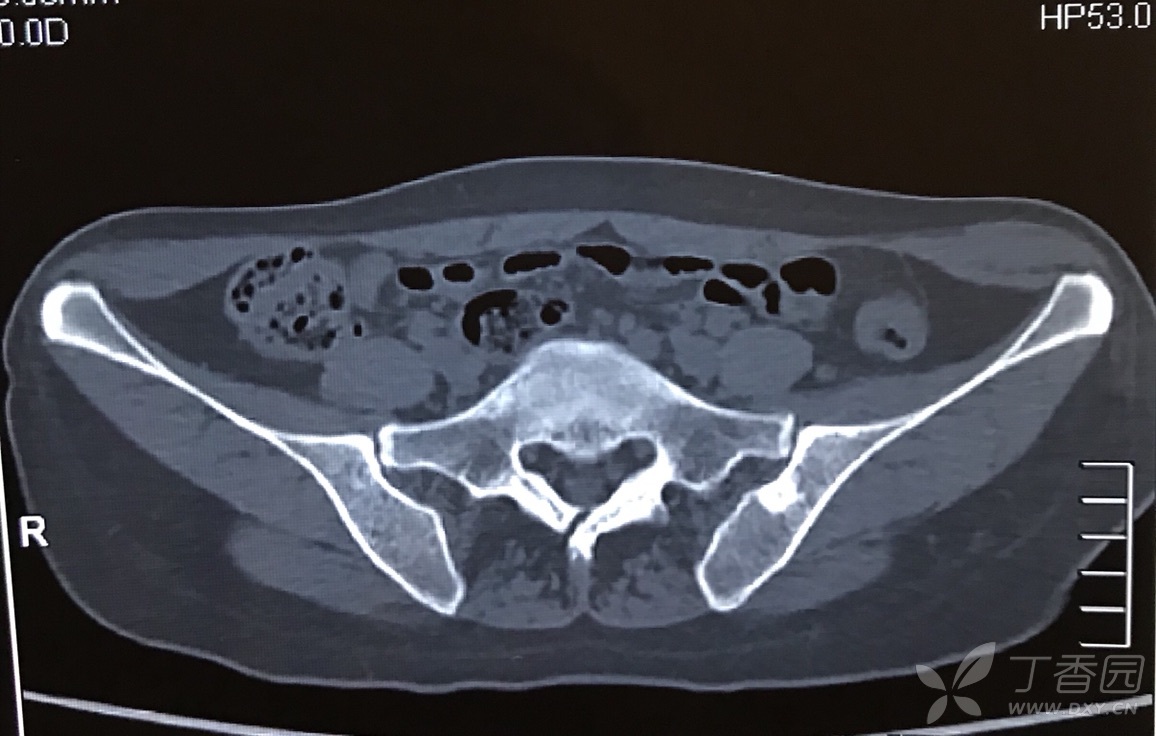

各位大师请判断,骨岛?骨纤?转移瘤?如何进行下一步?

骨扫描显示没有高活性,与低级骨内骨肉瘤相反.骨岛有可能很大.